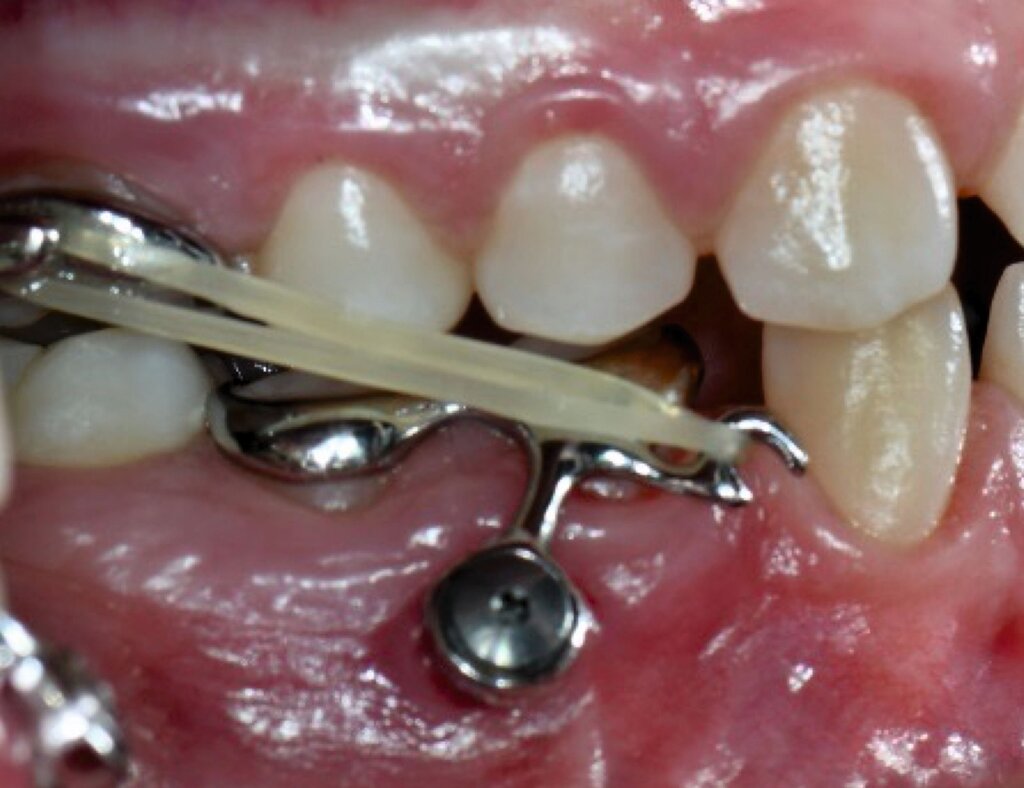

Auch die Herstellung zusätzlicher Elemente, wie beispielsweise Transpalatinalbögen aus Keramik-gefüllten 3-D-Druckkunststoffen, ist möglich (Abbildung 2c) [Thurzo et al., 2022], muss jedoch in großangelegten Studien noch auf eine ausreichende klinische Suffizienz untersucht werden. Weiter bieten 3-D-gedruckte Transferguides die Möglichkeit des „Indirekten Klebens“ [Deahl et al., 2007; Bozelli et al., 2013; Li et al., 2019; Sabbagh et al., 2022], wobei die Bracketpositionierung bereits vor dem Einsatz digital festgelegt und schließlich durch den Transferguide intraoral übertragen wird (Abbildung 2d). Neben einer verkürzten Stuhlzeit erlaubt dieses Verfahren eine besonders hohe Genauigkeit der Bracketpositionierung.

Weiter erlauben hochindividuelle 3-D-gedruckte Designs die Therapie von skelettalen Fehlständen, beispielsweise in der Therapie defizitärer Maxillae [Pasqua et al., 2022; Bazargani et al., 2023; Ludwig et al., 2024] oder im Rahmen der nonoperativen oder postoperativen Prognathie-Behandlung [Hodecker et al., 2023]. Auch die Umsetzung skelettal verankerter Apparaturen mittels nichtmetallischer 3-D-Druckmaterialien findet in einzelnen Fällen Anwendung (Abbildung 3b). Zum Einbringen der Miniimplantate eignen sich sogenannte 3-D-gedruckte „Insertions-Guides“, die nach vorheriger digitaler Planung der Miniimplantat-Position, eine hochgenaue Insertion ermöglichen [Wilmes et al., 2022; Wilmes et al., 2022]. Die virtuelle Planung der Minischraubeninsertion ermöglicht eine sichere und nachvollziehbare Evaluation sämtlicher relevanter Gewebe, um die ohnehin geringen Risiken weiter zu minimieren. Zusätzlich kann man die Biomechanik der digital geplanten kieferorthopädischen Apparatur ideal koordinieren und – wenn man möchte – die Minischrauben und die Apparatur in einer Sitzung einsetzen.